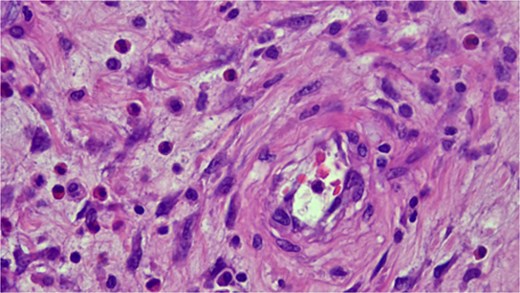

Histopathologic examination showing spindle cells in a fibromyxoid stroma with a mixed inflammatory reaction, consistent with an IFP (Vanek’s tumor).

Microscopically, IFPs are composed of spindle-shaped, mononuclear cells arranged in a whorled or "onion skin" pattern around blood vessels and glands. The inflammatory infiltrate includes eosinophils, lymphocytes, macrophages, mast cells, and blood vessels, with a matrix of fine or collagen-rich fibrils. The classic gastric type, rich in eosinophils, has many spindle cells but minimal collagen, while the intestinal type is less cellular and more collagen-rich [16].